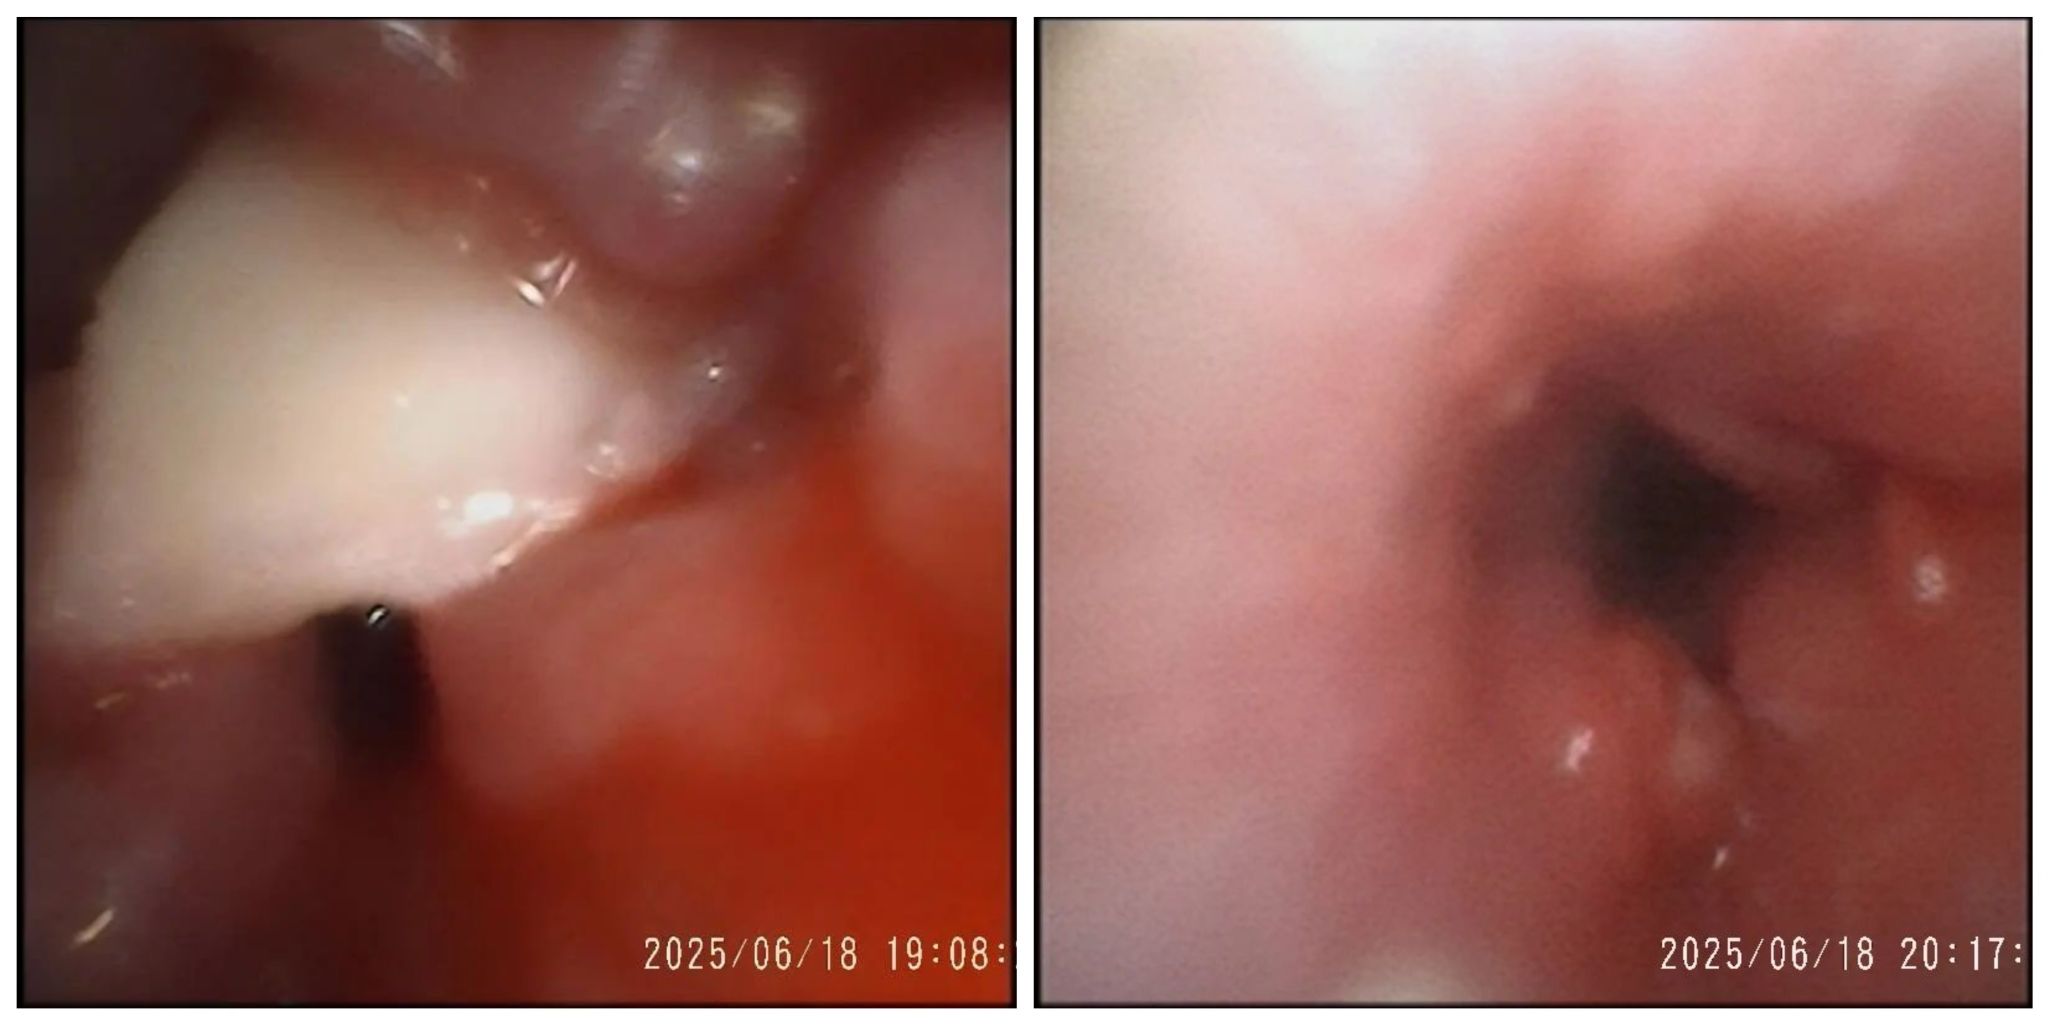

气道异物取出前后对照图

由于患儿异物堵塞右主支气管长达1月,导致局部气管壁肉芽组织过度增生,肉芽包裹异物,形成复杂气道环境,增加异物取出难度。在麻醉科全程护航下,儿科二区气管镜团队孙萌萌、张冰雪医生、董佳乐护士凭借丰富气管镜操作经验及默契配合,历时1小时成功取出半颗完全阻塞气道的花生碎块。术后患儿咳喘明显减轻,右肺听诊呼吸音恢复。半颗花生引发的"气道危机",在儿科二区医护团队的精准施救下成功化解。